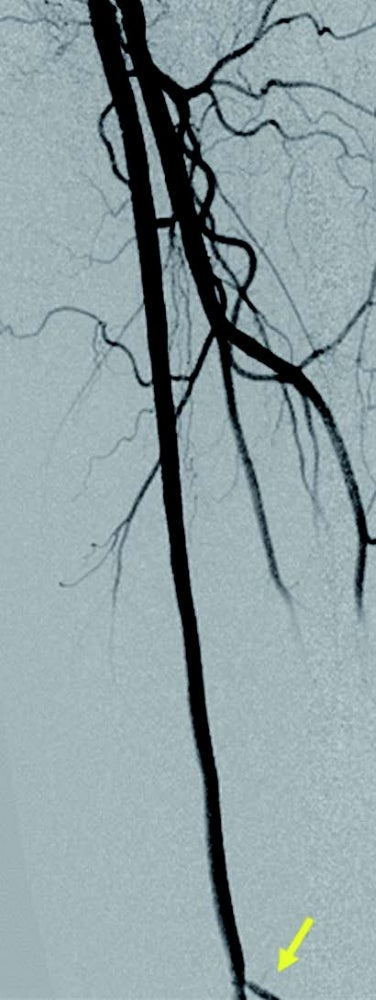

左浅大腿動脈閉塞(図1):右鼠径部を穿刺(6 Frシース)しcrossover後、順行性に0.014 inchマイクロカテーテルを使用して0.014 inchガイドワイヤー(先端荷重1 g→40 g)を進め貫通、IVUS catheterで真腔を捕らえていることを確認。5.0 mm径バルーン(non-compliant balloon)で拡張後解離が生じ、末梢にバイアバーン® ステントグラフト5.0 × 150 mm、中枢に6.0 × 150 mmの2本を留置。病変の末梢には発達した1本の側副血行路を伴い、側副血行路の中枢側に健常部位があったため、側副血行路をjailせずバイアバーン® ステントグラフトを留置。5.0 mm径と6.0 mm径バルーン(non-compliant balloon)で後拡張して終了。(図2)